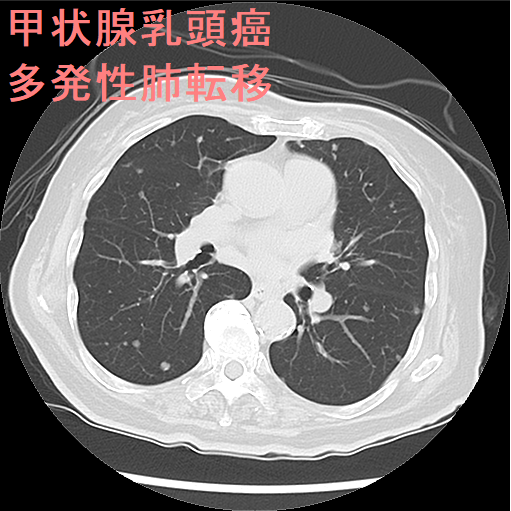

甲状腺乳頭癌 肺転移 CT画像。中-下肺野に、小粒状陰影が多数あります。

甲状腺癌の肺転移様式として、両側肺に、びまん性多発小結節を形成するのが普通です(上記肺X-p、CT画像)。孤立結節型は11.4%とされます。